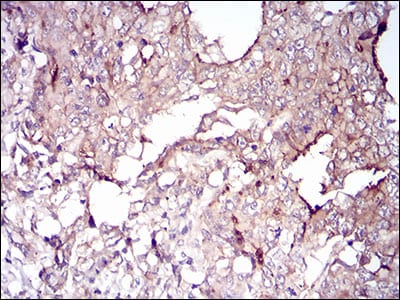

分类: 科研抗体货号: 30706别名: TRIM63; IRF; SMRZ; MURF2; RNF28应用: IHC反应种属: Human